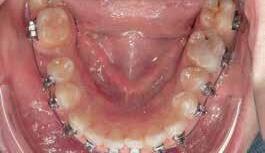

A 33 year old male presented to the orthodontic clinic referred by his prosthodontist . His main concern was the overeruption of maxillary right and left second molar due to bilateral loss of second and third mandibular molars that rendered the placement of prosthodontic implant and crown not possible. The patient had a 4 unit bridge, to replace missing maxillary right first and second premolar, with a root canal treatment and crown done on maxillary right lateral incisor and left second premolar. The patient’s main condition was to reduce the orthodontic system to a minimum with no visible appliances due to the nature of his work in sales.

Option 2

Placement of temporary anchorage devices (Miniscrew) in the buccal and palatal side of the maxillary second molars in order to orthodontically intrude those teeth and create the required biological space for implant and crown placement in the mandibular posterior molar region(Figure 3).

Interproximal reduction in the area between maxillary first and second molar is necessary to allow the intrusion of the second molar without being hindered by the proximal contact of the first molar.(figure 4)

Option 2 was the patient’s choice based on the fact that it saves tooth structure and integrity nonetheless he was informed about the possibility of failure of the miniscrews and the potential for discomfort due to contact between his tongue and the palatal miniscrews.

April 2021:

- Bonding of tubes on buccal and palatal surfaces of upper 2nd molars

- 2 Buccal (1.6 mm diameter 8mm length) infra-zygomatic mini screw on upper 2nd molars of each side were placed this high in order not to interfere with the intrusive movement.

- 2 Palatal (1.8 mm diameter 8 mm length) placed in the midpalatal suture and another halfway the distance between the left second molar and the mid-palatal suture .

- The mini-screws were placed in a way that the resultant forces on each side are 120-150 g of force leading to close to pure intrusion of 2nd molars .

Figure 3 Figure 4

The patient presented to the clinic every 6 weeks for chain replacement because slow intrusion is needed. The 2nd molar was blocked below the distal contact area of the 1st molar, monitored IPR was carried out between the 1st and 2nd molar on both sides to facilitate the intrusive movement. The treatment took 10 months with 7 appointments.